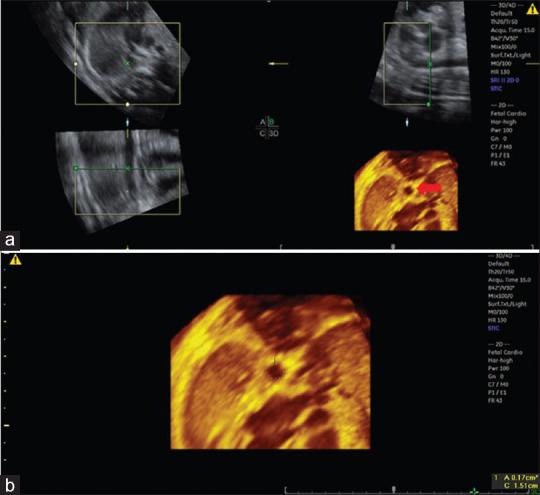

The objective of this study was to assess the ascending and descending aorta area measurements by three-dimensional (3D) ultrasound using spatiotemporal image correlation (STIC) in the rendering mode comparing these measurements with pregestational diabetic mothers and assessing the reproducibility of the method.

We carried out a retrospective cross-sectional study with 58 normal and nine fetuses from pregestational diabetic mothers between 20 and 33 + 6 weeks of gestation. Fetal heart volumes were acquired at the level of four-chamber view to obtain the reconstructed planes for the ascending and descending aorta areas in the rendering mode. Linear regression was performed to assess the correlation between the fetal aorta areas and gestational age (GA). To assess the intra- and interobserver reproducibility, we used the concordance correlation coefficient (CCC).

The mean ascending and descending aorta areas were 0.12 (0.02-0.48) and 0.11 (0.04-0.39) cm in normal fetuses, respectively. There was a moderate positive correlation between GA and ascending aorta area measurements (0.005676GA - 0.01283; = 0.53, < 0.0001) and strong positive correlation between GA and descending aorta area (0.01095GA - 0.1581; = 0.68, < 0.0001). We observed a weak intra- and interobserver reproducibility with CCC ranging from 0.05 to 0.91. The mean difference in the ascending and descending aorta area measurements of normal and fetuses of pregestational diabetic mothers was -0.03 cm ( = 0.276) and -0.03 cm ( = 0.231), respectively.

The fetal ascending and descending aorta area measurements obtained by 3D ultrasound using STIC in the rendering mode increased with GA in normal fetuses. The method showed weak intra- and interobserver reproducibility.